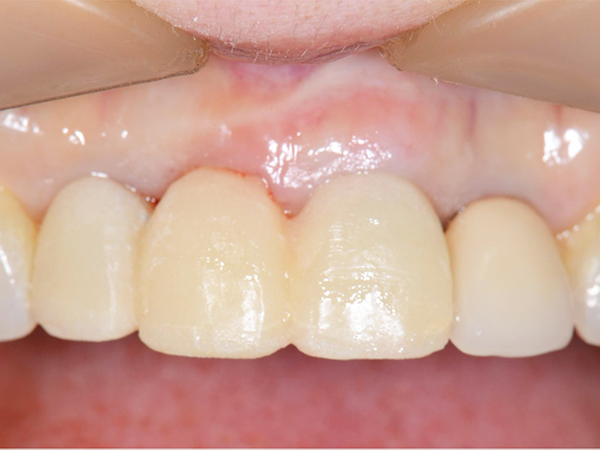

術後4ヶ月 仮歯の調整

1次手術時に製作した仮歯を外し、歯ぐきと周りの歯と調和するように仮歯の形を修正しました。

本症例では骨造成を同時に行ったため、唇側の歯ぐきの幅が減ることなく、きれいな状態を保っています。